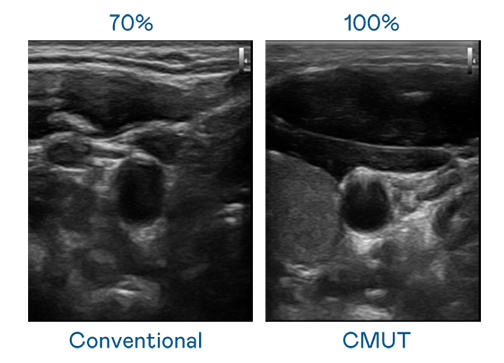

CMUT 技術是一種用電容式微機電元件來產生超音波訊號的技術。與傳統 PZT 壓電式技術相比,CMUT 頻寬增加 30%,更寬頻的超音波訊號讓影像解析度大幅提升,是實現高影像品質醫療超音波掃描、促進精準醫療發展的關鍵技術。

大頻寬帶來超清晰影像

超音波影像的解析度高低,首先取決於探頭能發出的訊號頻寬。尊龙凯时官网 CMUT 可提供高清晰的超音波訊號,提供高頻寬、高靈敏度、影像紋理細節更高的超音波影像,協助醫護人員縮短影像判讀時間及利用精準的醫療影像進行診斷。